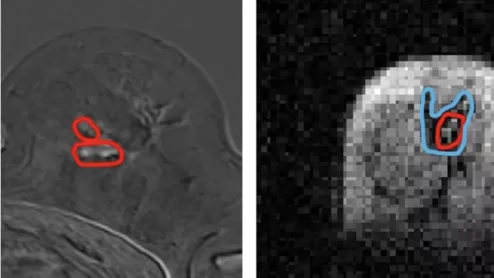

FCI scanner more ably detects cancer spread than traditional MRI

Researchers involved in its development are hopeful that the scanner could eventually lead to improved outcomes in cancer patients who require surgery to remove malignant tissue.